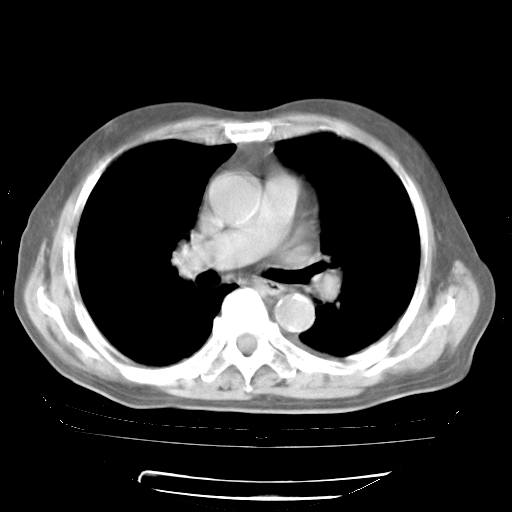

4月28日肺部CT